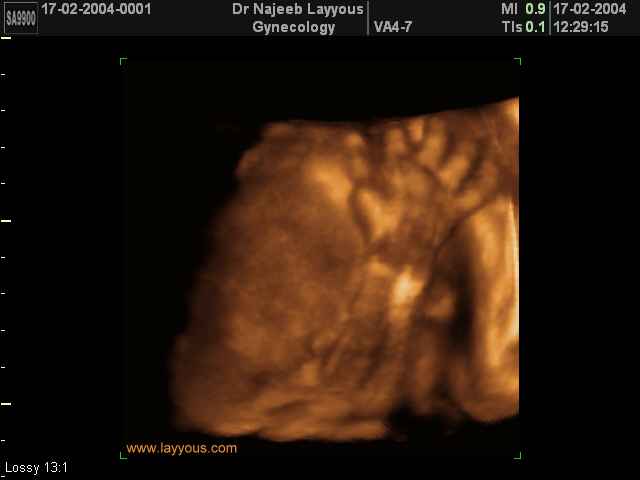

- 3D Fetal Limbs Ultrasound Scan Photos